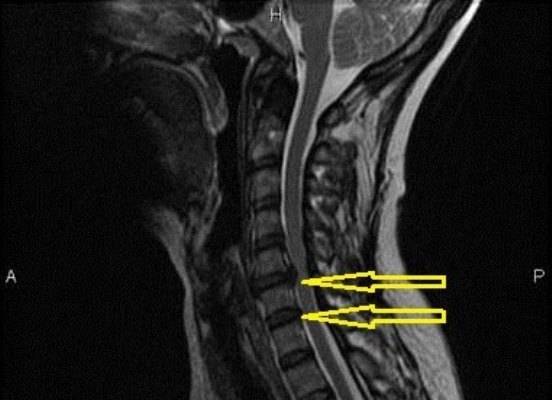

Поражение c5 – c6 позвонков

Шейный отдел позвоночника поражается реже, но при локализации патологии в этих местах наблюдаются следующие симптомы:

- головокружение и сильные головные боли;

- парезы в руках;

- повышение давления;

- шум в ушах и ухудшение зрения;

- боль в области шеи, которая отдает в плечо,руку и под лопатку.

Какая самая опасная грыжа шейного отдела позвоночника?

Опасное осложнение грыжи шейного диска — миелопатия. Оно развивается, когда грыжевое образование выходит в спинальный канал. Внутреннее пространство канала сужается, и вещество спинного мозга сдавливается.